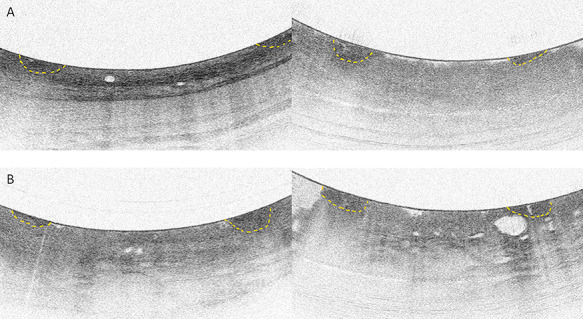

(A) Two volumetric laser endomicroscopy (VLE) regions of interest with nondysplastic Barrett’s esophagus. The left image clearly displays a normal esophageal layering of the mucosa. The right image contains the VLE feature lack of layering; however, there is no visible increased signal surface intensity or the presence of multiple irregular glands. (B) Two VLE regions of interest with Barrett’s neoplasia. Both images contain the abnormal VLE features multiple irregular glands and lack of layering. In the VLE images, the laser marks are visible as small areas of high surface signal intensity indicated by the yellow delineations.